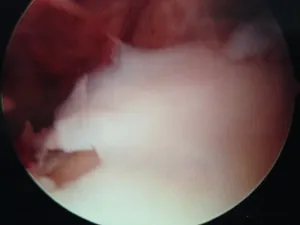

A series of intraop ankle arthroscopy pics of synovial chondromatosis with OCD talus and tibia and microfracture.

Pic of one of the nodules inside the ankle joint.